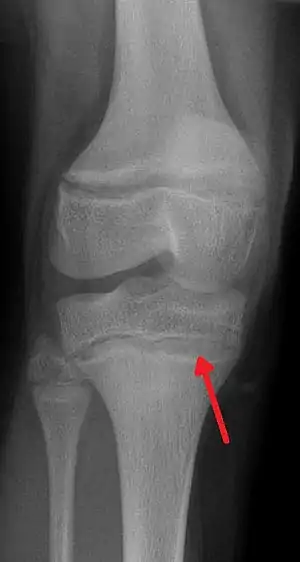

| An X-ray demonstrating the characteristic finding of lead poisoning in humans—dense metaphyseal lines | |

Exposure to lead can occur by contaminated air, water, dust, food, or consumer products.[2] Lead poisoning poses a significantly increased risk to children as they are far more likely to ingest lead indirectly by chewing on toys or other objects that are coated in lead paint.[2] The amount of lead that can be absorbed by children is also higher than that of adults. Exposure at work is a common cause of lead poisoning in adults with certain occupations at particular risk.[7] Diagnosis is typically by measurement of the blood lead level.[2] The Centers for Disease Control and Prevention (US) has set the upper limit for blood lead for adults at 10 µg/dl (10 µg/100 g) and for children at 3.5 µg/dl,[8] previously before October 2021 5 µg/dl[9][10] Elevated lead may also be detected by changes in red blood cells or dense lines in the bones of children as seen on X-ray.[4]

Blood lead levels are an indicator mainly of recent or current lead exposure, not of total body burden.[207] Lead in bones can be measured noninvasively by X-ray fluorescence; this may be the best measure of cumulative exposure and total body burden.[37] However this method is not widely available and is mainly used for research rather than routine diagnosis.[103] Another radiographic sign of elevated lead levels is the presence of radiodense lines called lead lines at the metaphysis in the long bones of growing children, especially around the knees.[208] These lead lines, caused by increased calcification due to disrupted metabolism in the growing bones, become wider as the duration of lead exposure increases.[208] X-rays may also reveal lead-containing foreign materials such as paint chips in the gastrointestinal tract.[26][208]